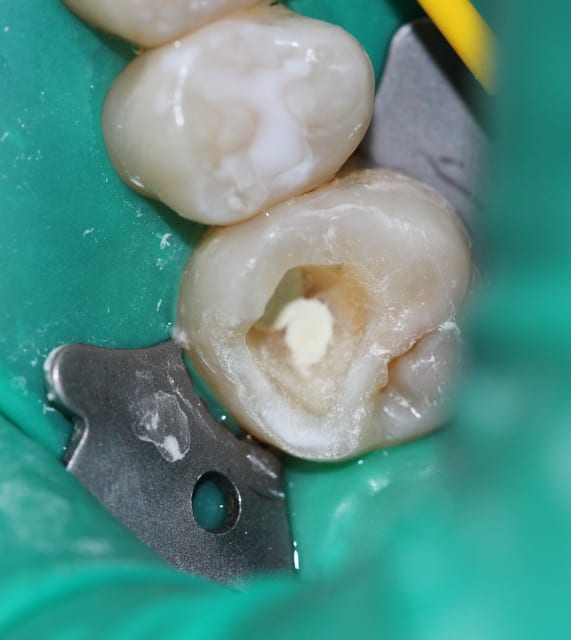

endo1_fye5ff.jpg

Voir le message contenant cette image